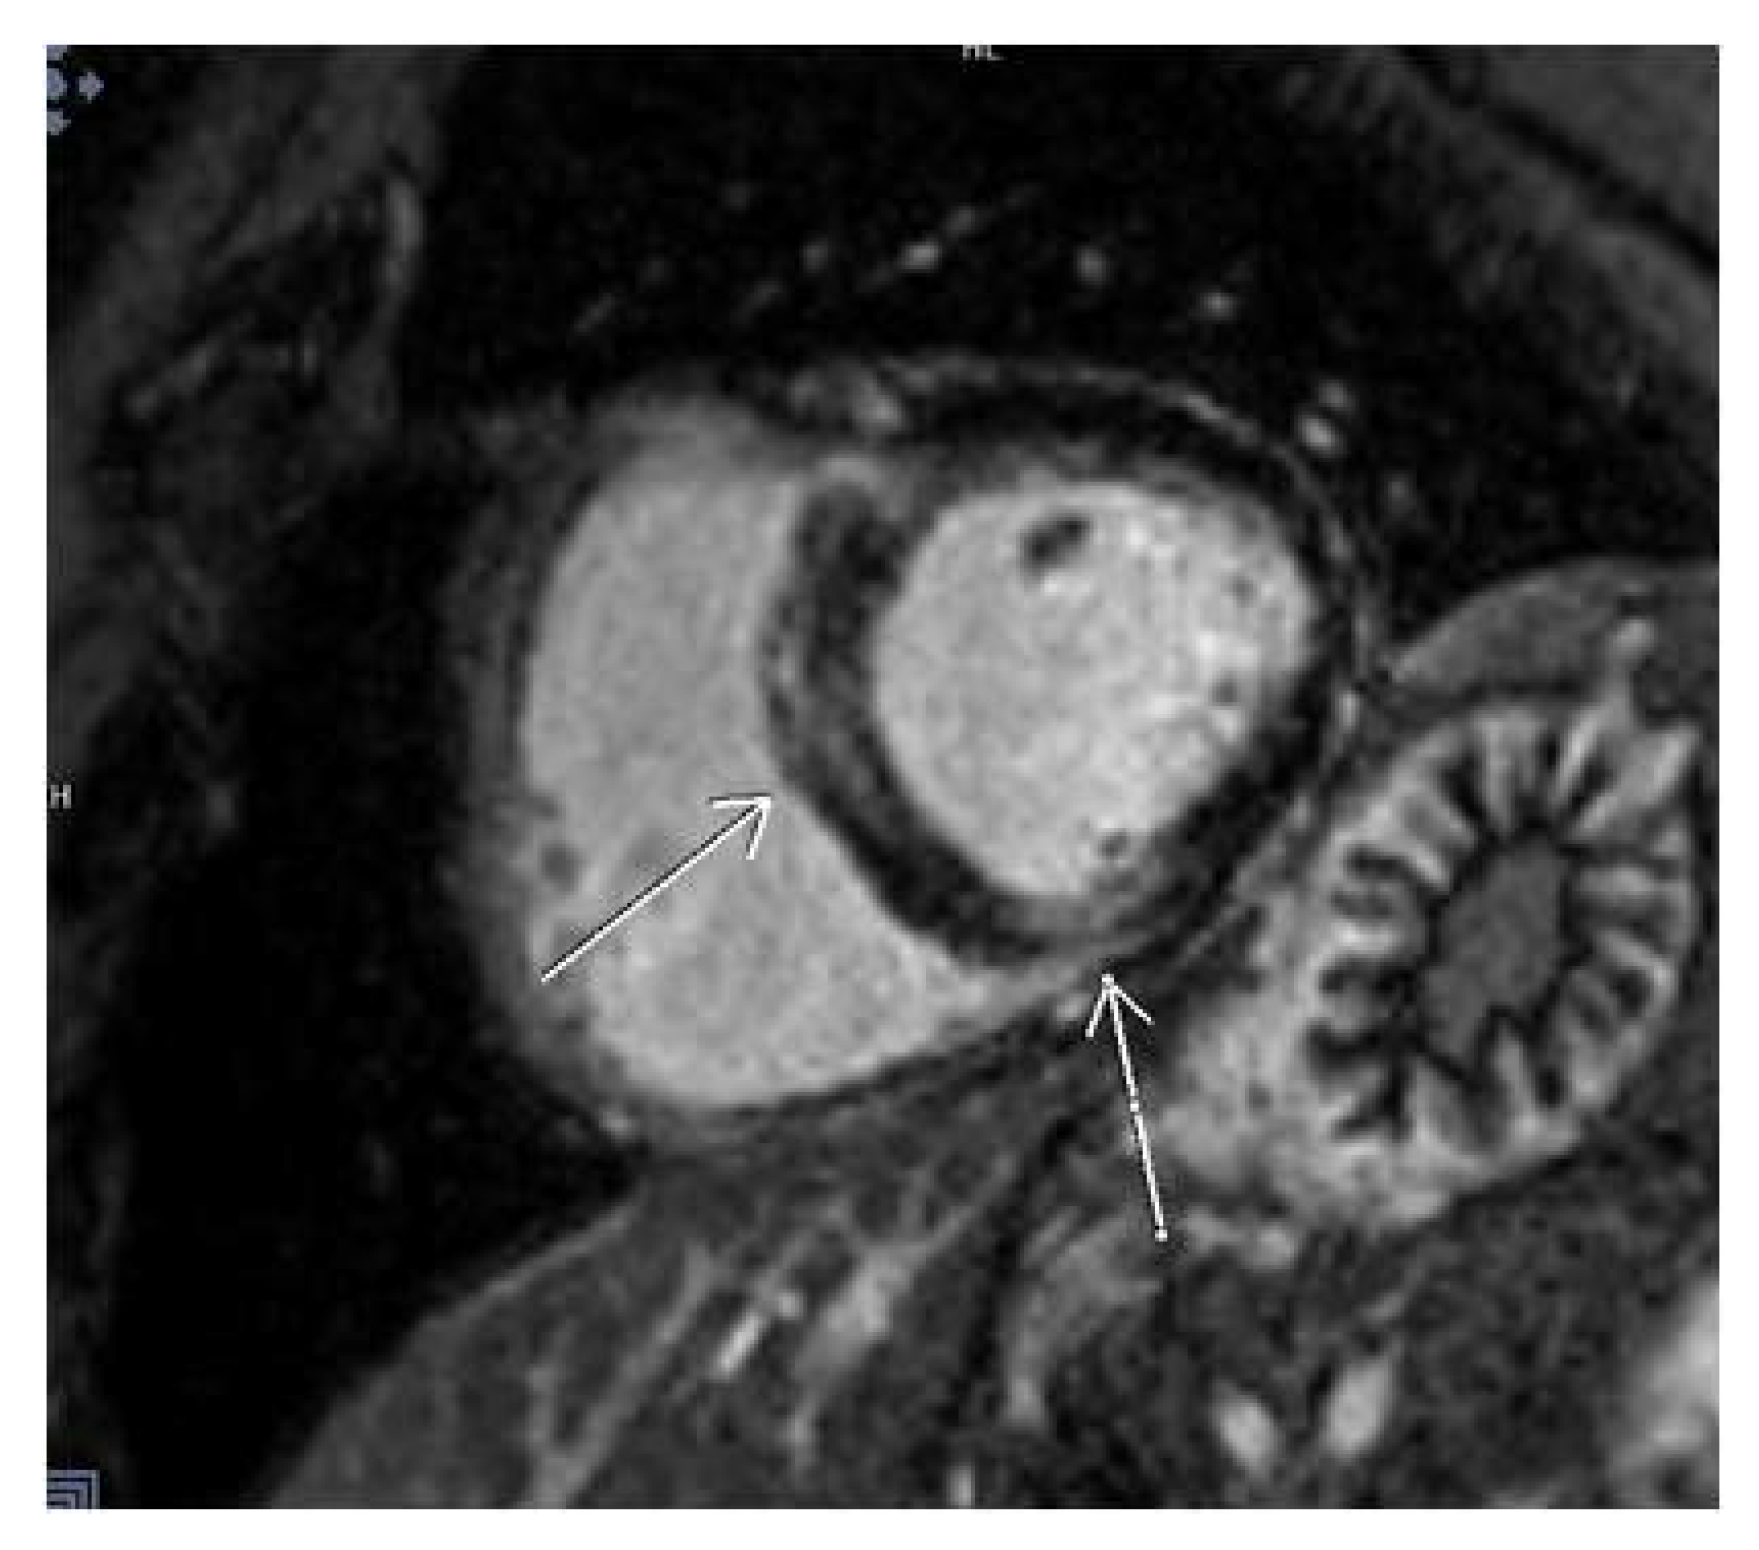

3.2. CMR Findings

3.5. LGE Localization